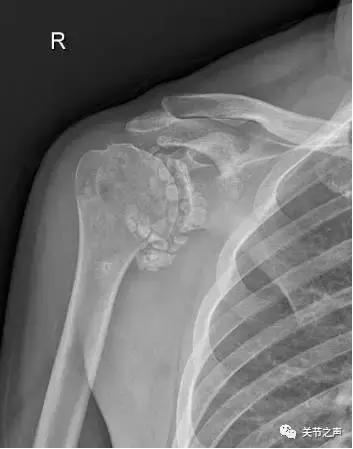

关节腔里的“珍珠”,就是我们常说的关节游离体,膝关节最多见,其次是肩关节。这种“珍珠”大多是一种良性肿瘤,叫滑膜软骨瘤病。

关节里长珍珠的症状:关节疼痛、卡压交锁例如:前不久,一位来自肇庆的许大姐因肩关节疼痛慕名来到暨南大学附属第一医院郑小飞主任门诊,X片显示他的肩关节长满了密密麻麻的“珍珠”。幸运的是,微创关节镜取“珍珠”是我们的看家本领,郑主任通过3个1cm的小切口就把他关节腔里的游离体全部取出,术后第二天开始康复功能锻炼。

除了肩关节,髋、膝、踝、肘、腕几乎全身各个关节都有可能长珍珠。

重要提示:关节腔游离体一旦发现,要尽早取出。

若等到疼痛症状非常严重、卡压交锁非常频繁时,关节内软骨大多已经磨损得非常严重了,继发造成的创伤性关节炎不可逆转。